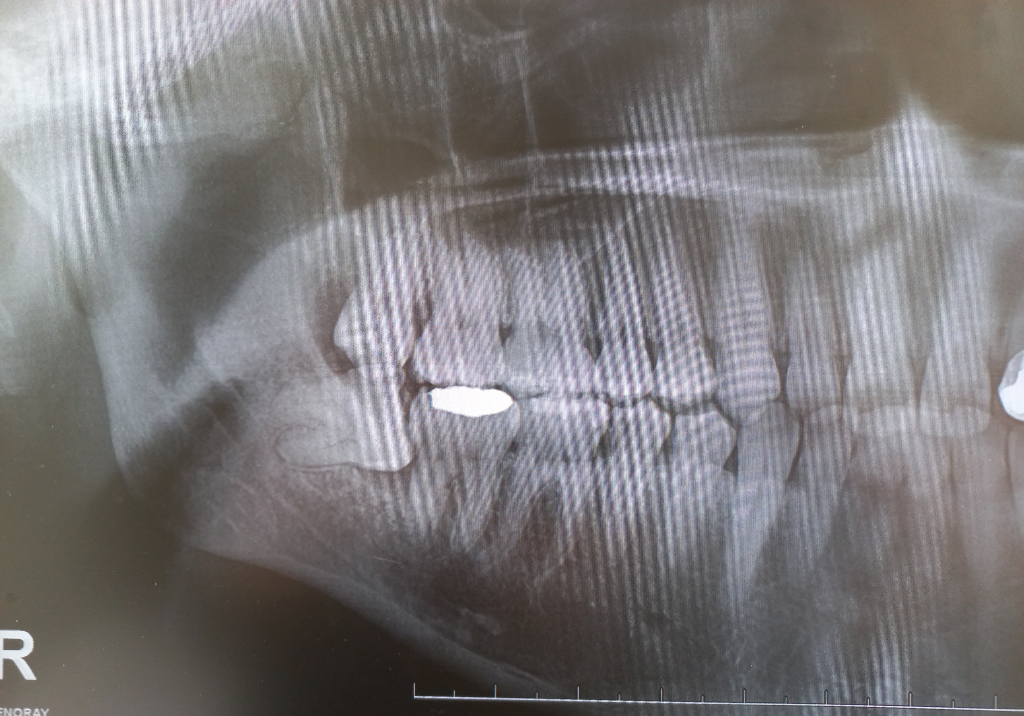

A치과에서는 사이충치 1곳 치료필요하고 사랑니 우측 하단 사랑니 1개 빼야한다고 했고 B치과 가봤더니 충치 8~9개 치료해야하고 사랑니도 4개 다 뽑아야한다고 하네요

우측 하단 사랑니는 무조건 뽑아야되는 사랑니인거 같고 나머지 사랑니도 관리가 안될꺼 같으니 뽑으라고 말한거 같습니다. 그리고 엑스레이상으로 인접면 충치가 다수보이긴 합니다.

3. 사랑니의 경우 파노라마 사진 상에서는 아래 2개는 일단 뽑는 것이 좋을 것 같습니다. 특히 아래 우측 사랑니는 옆 어금니에도 영향을 주고 있기 때문에 너무 늦지 않게 뽑는 것이 좋을 것 같습니다.